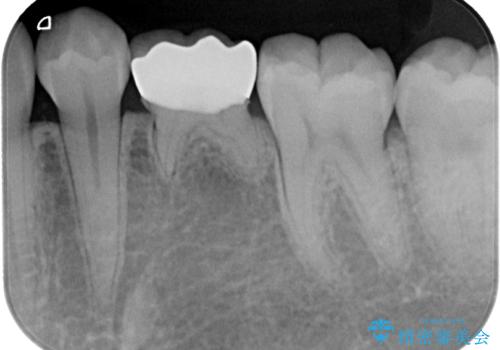

レントゲン上で金属の詰め物(メタルインレー)の下に虫歯を認めた為、オールセラミッククラウンでの治療と、乳歯なので予後を考えインプラントによる補綴治療もご提案しましたが、患者様の強い希望によりオールセラミッククラウンでの治療となりました。

拡大鏡視野下で、金属の詰め物(メタルインレー)、虫歯の除去を行い、オールセラミッククラウンに適した形に整えました。

歯と歯茎の間に圧排糸と言われる糸を入れてシリコーン印象材にて型どりをしました。

治療後特に問題もなく見た目、噛み合わせともに満足していただけました。